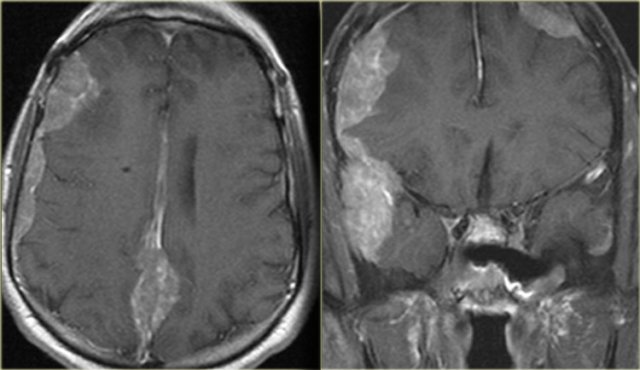

On the left images of a patient was initially diagnosed with a glioblastoma multiforme. There are abnormalities in both frontal lobes.

Notice however the abnormal tissue in the frontal sinus (yellow arrow), subperiosteal abscess (red arrow) and the fluid-fluid level (green arrow) in the large intracranial lesion which has ring enhancement.

All abnormalities are continuous meaning there is frontal bony destruction.

The restricted diffusion also supports the diagnosis of brain abscess.

This is a subperiosteal abscess and osteomyelitis of the frontal bone, usually with a soft tender swelling of the forehead.

This is also called Pott's puffy tumor after Sir Pott, an English surgeon who first described this entity.

Brain abscess Brain abscess

Brain abscess (2)

On the left images of another patient, who had recently been treated for sinusitis and now presented with a seizure. The CT shows an abnormality in the left temporal lobe with shaggy thick rim enhancement, and a large amount of vasogenic edema. This is also a brain abscess, most probably due to reflux of bacteria into cranial veins and the venous plexus around the cavernous sinus.